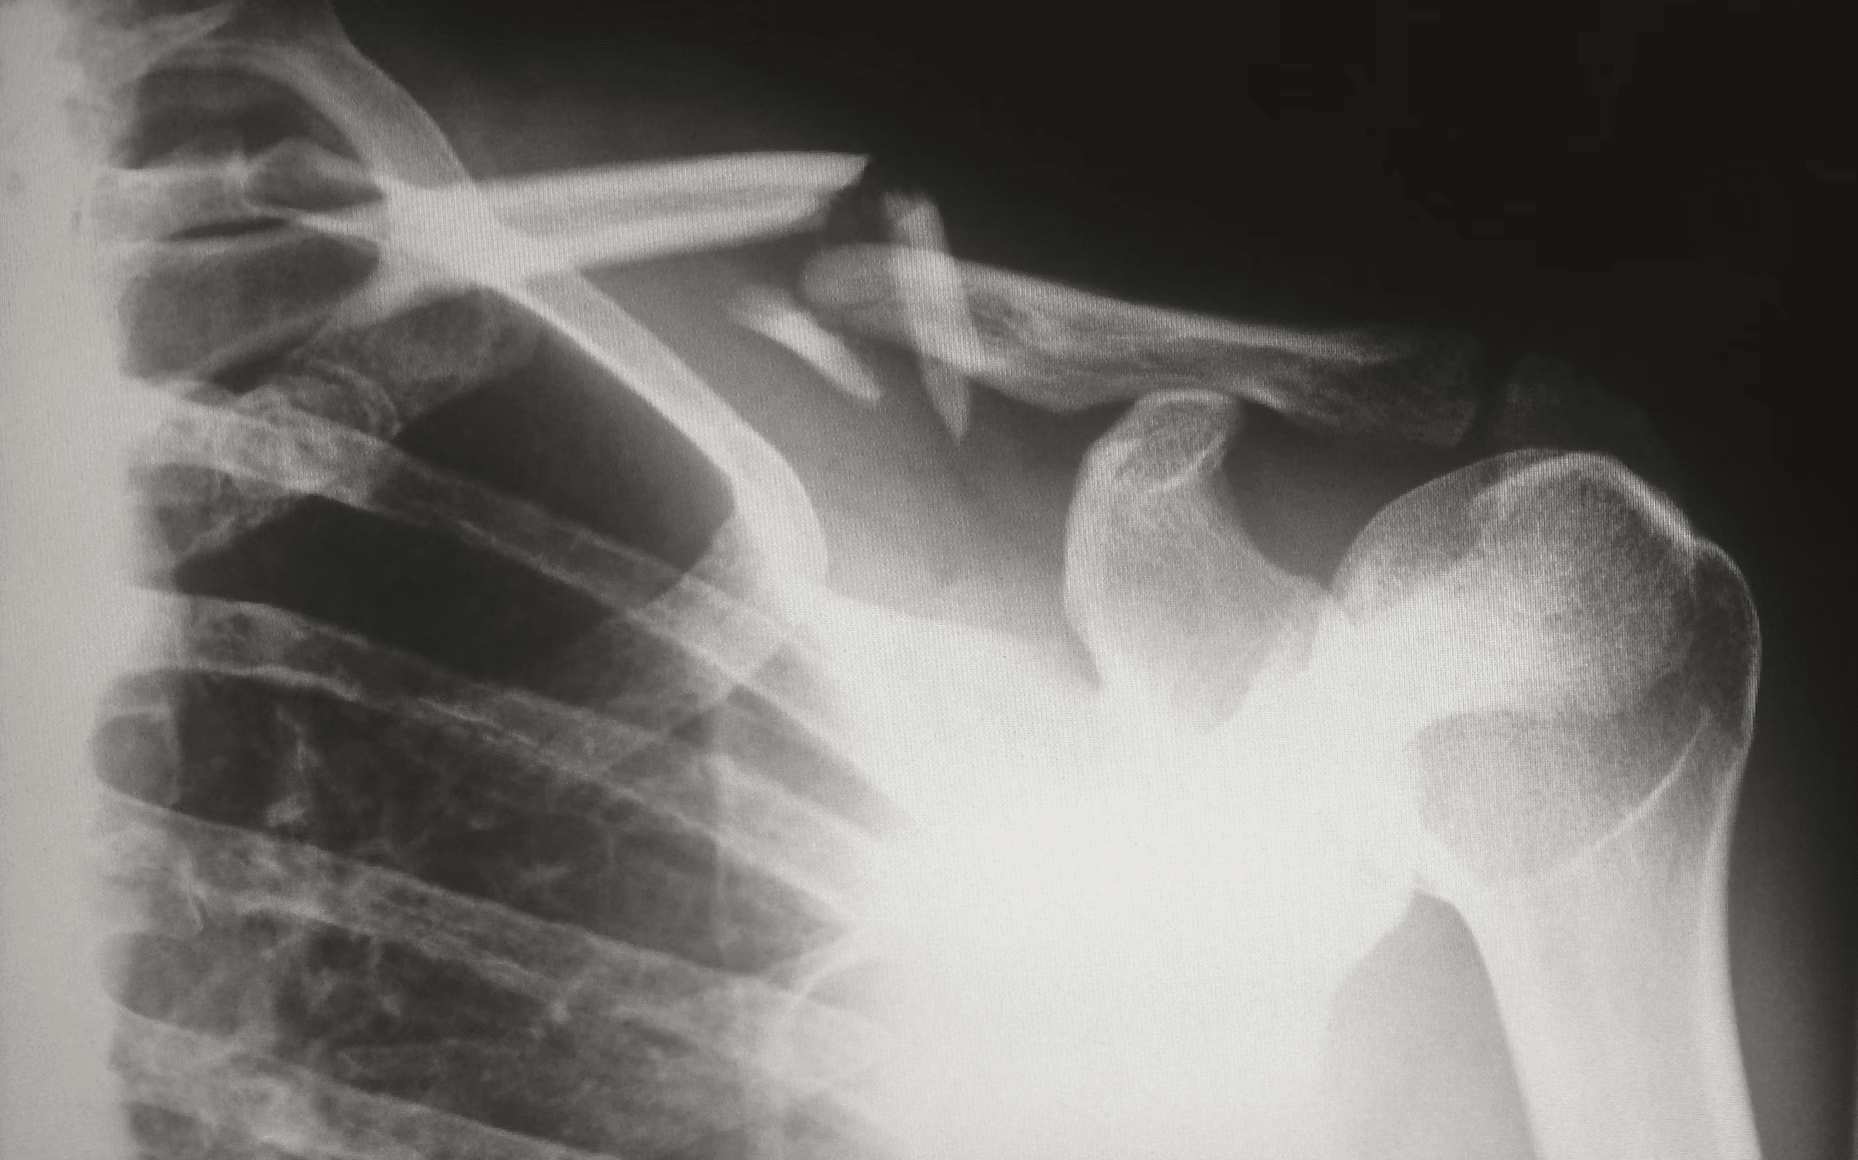

Takové vykloubení ramene, natažení vazů nebo zlomeniny klíční kosti dokáží nadělat spoustu problémů, a to i potom, co se zahojí. Po úrazech se totiž často tvoří jizvy a dochází k omezení hybnosti. A to může mít opět za následek bolesti. Podobně i po operacích ramene často i měsíce (někdy i roky) přetrvává bolestivost kvůli srůstům nebo omezenému rozsahu pohybu. Obnova plné funkčnosti ramene a zmírnění bolesti je možná, ale jedině s rehabilitacemi – na které chodíte pravidelně a samozřejmě poctivě cvičíte i mimo ně.